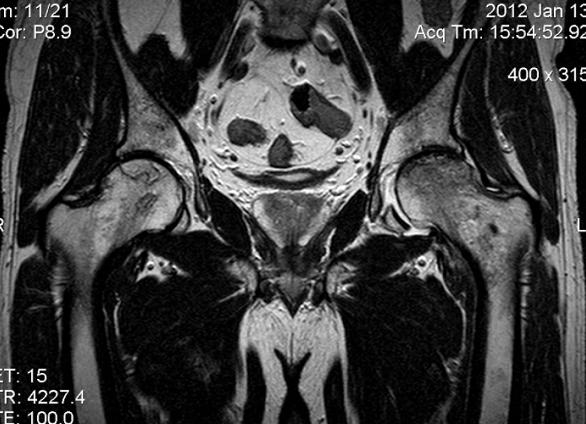

МРТ тонкого и толстого кишечника. Гидро МРТ. Колоноскопия

Существует множество эффективных и достоверных методов выявления патологий желудочно-кишечного тракта. Самыми информативными считаются гидро МРТ, колоноскопия и ирригоскопия, о которых и пойдет речь.